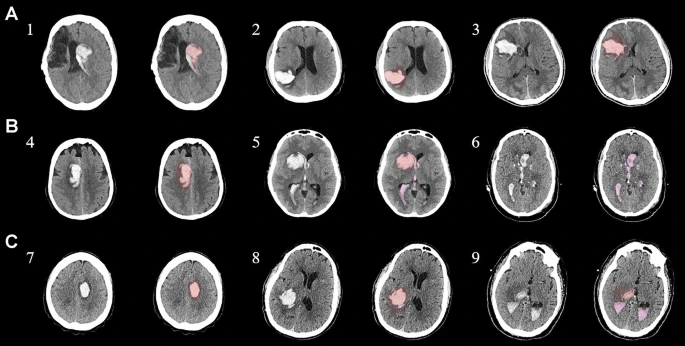

資格標準包括非外傷性幕上血腫小于60mL和格拉斯哥昏迷評分大于5。所有患者均在神經科學重癥監護病房接受監測,以了解間充質干細胞/基質細胞輸注的安全性和耐受性以及不良事件。我們還探索了使用細胞因子作為生物標志物來評估對細胞療法的反應。我們篩選了140名患者,將符合資格標準的9名患者分為三個劑量組:50萬個細胞/kg、100萬個細胞/kg和200萬個細胞/kg。補充圖1和補充表1中列出了報告試驗綜合標準圖和詳細的資格標準。

圖1:每個間充質干細胞治療患者按組的原始非對比計算機斷層掃描和分割結果

本研究納入2018年1月1日至2020年10月31日發病168小時內發生急性ICH的患者。間充質干細胞被靜脈注射給9名患者(5名女性,4名男性),平均年齡(范圍)為61(36-84)歲。表1總結了人口統計學和臨床??特征 。出于描述目的,患者按照入組順序獲得編號,并連續分配到三組中的一組,每組三人。根據模型 2 分割,ICH體積范圍為0.1至54.9mL(平均ICH體積為23.5mL)。5例ICH累及局部腦葉,其余則位于基底節或外囊深處。在三名患者中,ICH位于丘腦(圖1),在一名患者中,血腫位于多個腦結構(即尾狀核、殼核和蒼白球)。平均而言,MSC在ICH后3天進行注射。